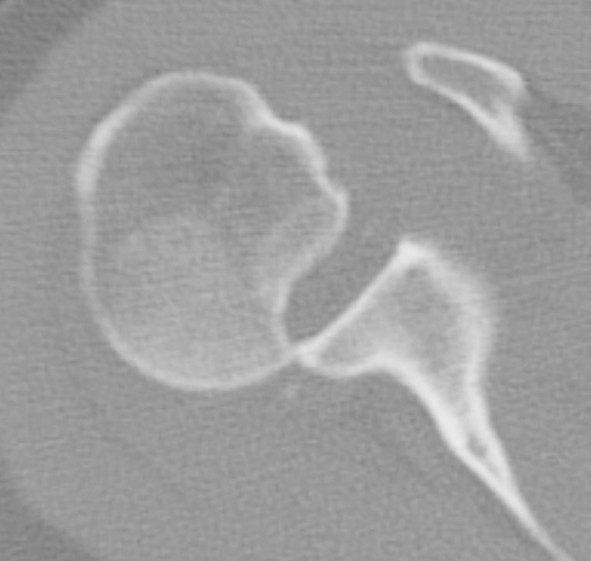

CT scan

Confirms dislocation

Reverse Hill Sachs

Humeral head defect

- caused by impaction of anterior humeral head on posterior glenoid

- intra-articular

- measured as a percentage of the articular surface

Lesser tuberosity fractures

Posterior glenoid fractures / bony bankart